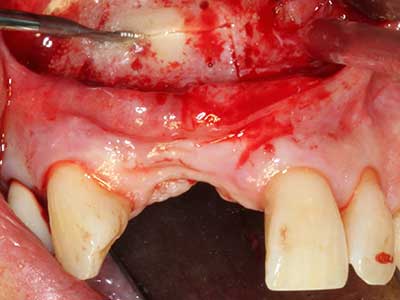

Фиг. 1: Препарация на костно покритие с Piezomed (W&H Залцбург, Австрия).

Фиг. 2: Хоризонтален и вертикален латерално-максиларен дефект с висока линия на усмивката с индикация за пре-реконструкция за имплант.

Фиг. 6: След препарация на мукопериосталната клапа.